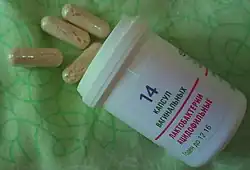

Research has shown that the presence of L. acidophilus can produce a variety of probiotic effects in humans, such as acting as a barrier against pathogens, assisting in lactose digestion, enhancing immune response, and reducing cholesterol level. L. acidophilus must exist in concentrations of 10^5 - 10^6 c.f.u (colony-forming units) per mL in order for these effects to be seen.[8] A study conducted at the Wake Forest School of Medicine examined the effects of L. acidophilus on the structure and composition of the gut microbiome of mice with respect to the age of the mice. The research established the importance of the interactions between microbes within a gut microbial environment on the overall health of the organism, and the data showed that mice supplemented with L. acidophilus had reduced proteobacteria levels, and increased levels of other probiotic bacteria when compared to other mice of similar age.[23] Another study conducted at Maranatha Christian University studied the impact of L. acidophilus cell free supernatants (a liquid medium containing the metabolites produced by microbial growth)[24] on the growth pattern of Salmonella typhi, the microbe associated with Typhoid fever. The study showed that the presence of L. acidophilus metabolites significantly inhibited the growth curves displayed by S. typhi,[25] supporting the idea that L. acidophilus presence has a positive impact on the species makeup of a gut microbial community, providing the organism with intestinal health benefits. The innate immune system of L. acidophilus also produces antimicrobial peptides.[26] The group of short peptides found there have shown antimicrobial properties such as their strength against viruses and other cell types, including cancer cells.[27] There is also some evidence supporting the use of a symbiotic gel (containing L. acidophilus) in treating gastrointestinal symptoms in patients who had received a hemodialysis treatment. This gel also reduced the occurrence of vomit, heartburn, and stomachaches. Further study concerning this subject is needed to draw firm conclusions.[28]

In 2023, Lactobacillus acidophilus was the 297th most commonly prescribed medication in the United States, with more than 400,000 prescriptions.[29][30]

As stated in a journal from the American Dairy Science Association, "Lactobacillus acidophilus is a commercial strain and probiotic that is widely used in the dairy industry to obtain high-quality fermentation products."[7] Increased levels of beneficial bacteria, and decreased levels of pathogenic bacteria within the intestine due to the consumption of fermented milk containing strains of L. acidophilus has a range of probiotic effects. Reduced serum cholesterol levels, stimulated immune response, and improved lactic acid digestion are all probiotic effects associated with intestinal L. acidophilus presence. L. acidophilus was also effective in reducing Streptococcus mutans levels in saliva, as well as decreasing risk factors associated with the development of nonalcoholic fatty liver disease.[7] The strain of L. acidophilus that has been most widely researched, and is most widely used as a probiotic and is referred to as NCFM.[1]